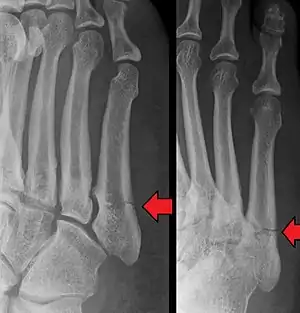

Jones fracture as seen on Xray

The fracture typically occurs when the toes are pointed and the foot bends inwards.[6][2] This movement may occur when changing direction while the heel is off the ground such in dancing, tennis, or basketball.[9][10] Diagnosis is generally suspected based on symptoms and confirmed with X-rays.[3]

Diagnostic x-rays include anteroposterior, oblique, and lateral views and should be made with the foot in full flexion.

Other proximal fifth metatarsal fractures exist, although they are not as severe as a Jones fracture. If the fracture enters the intermetatarsal joint, it is a Jones fracture. If, however, it enters the tarsometatarsal joint, then it is an avulsion fracture caused by pull from the peroneus brevis. An avulsion fracture is sometimes called a Pseudo-Jones fracture or a Dancer's fracture.

This injury should be differentiated from the developmental "apophysis" which is the secondary ossification center of the metatarsal bone. It is normally occurring at this site in adolescents. Differentiation is possible by characteristics such as absence of sclerosis of the fractured edges (in acute cases) and orientation of the lucent line: transverse (at 90 degrees) to the metatarsal axis for the fracture (due to avulsion pull by the peroneus brevis muscle inserting at the proximal tip) – and parallel to the metatarsal axis in the case of the apophysis.